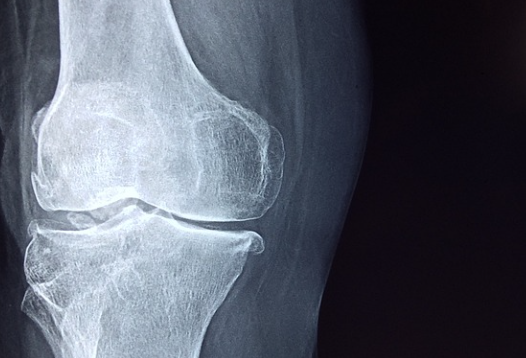

관절염의 가장 흔한 형태는 골관절염으로, 뼈 사이의 연골이 시간이 지남에 따라 마모되어 통증, 뻣뻣함 및 염증을 유발할 때 발생합니다.

골관절염의 초기 증상에는 특히 활동 후 발생하는 관절 통증이 포함될 수 있습니다.

- 영향을 받는 관절 주변의 붓기 또는 압통

- 운동 범위의 어려움

- 관절에서 딸깍거리거나 갈라지는 소리